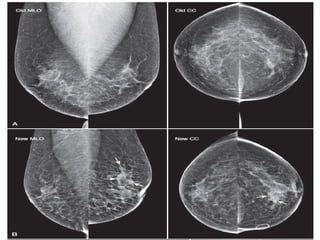

Asymmetries

Findings that represent unilateral deposits of fibroglandular tissue not

conforming to the definition of a mass.

Asymmetry as an area of fibroglandulair tissue visible on only one

mammographic projection, mostly caused by superimposition of normal breast

tissue.

Focal asymmetry visible on two projections, hence a real finding rather than

superposition.

This has to be differentiated from a mass.

Global asymmetry consisting of an asymmetry over at least one quarter of the

breast and is usually a normal variant.

Developing asymmetry new, larger and more conspicuous than on a previous

examination.

Here an example of a focal asymmetry seen on MLO

and CC-view.

Local compression views and ultrasound did not show

any mass.

Here an example of global asymmetry.

In this patient this is not a normal variant, since there are associated features,

that indicate the possibility of malignancy like skin thickening, thickened septa

and subtle nipple retraction.

Ultrasound (not shown) detected multiple small masses that proved to be

adenocarcinoma.

The PET-CT shows diffuse infiltrating carcinoma.